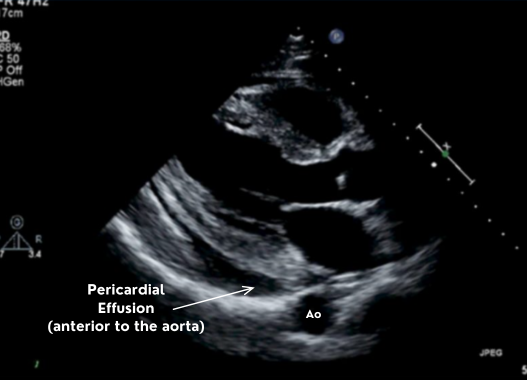

Parasternal Long-Axis (PLAX)

The parasternal long axis gives you the descending aorta which is the single best landmark for distinguishing pericardial from pleural fluid.

Fluid posterior to the aorta → pleural.

Fluid anterior to the aorta → pericardial.

pericardial effusion on parasternal long axis plax